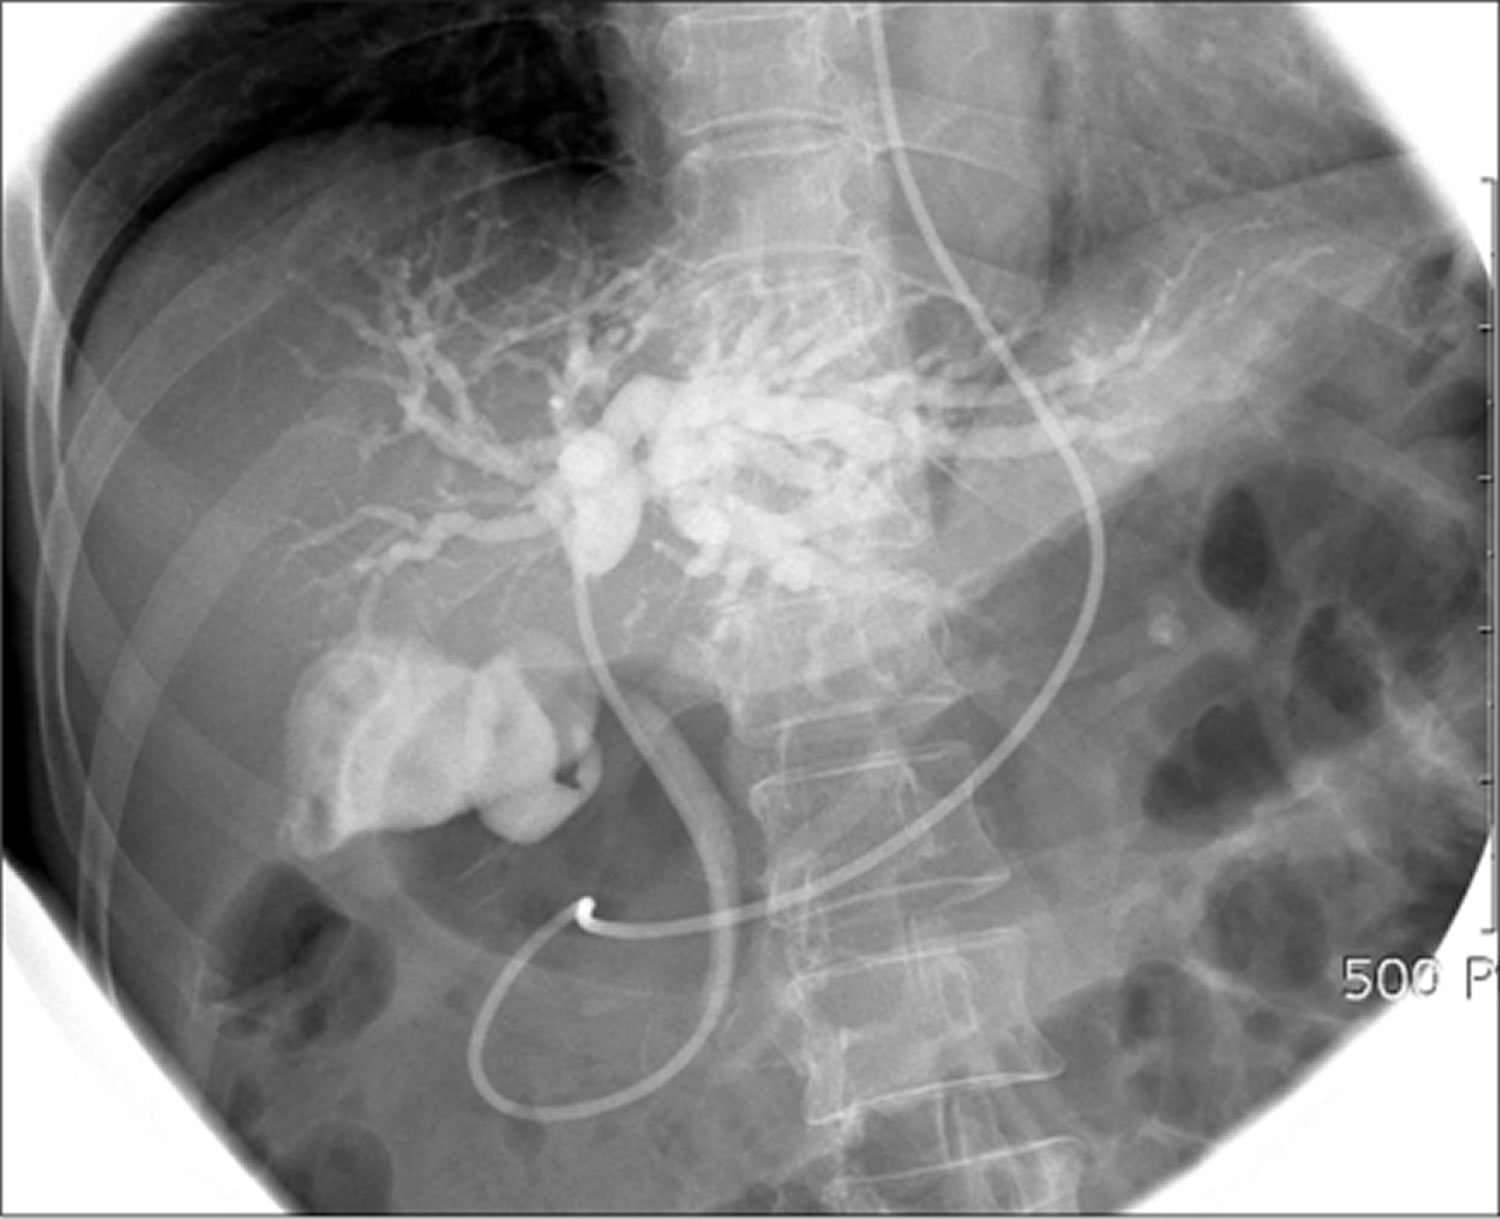

ERCP with therapeutic placement of selfexpanding metallic stent What Is Ercp Stent Placement Stents are plastic or metal devices used to widen a blocked or narrowed passage. A duct may become narrow or blocked due to scar tissue or a tumour. The results of this can allow doctors to visualise where your blockage is and treat it appropriately. Endoscopic retrograde cholangiopancreatography (ercp) is an invasive procedure used for the diagnosis and treatment of.. What Is Ercp Stent Placement.